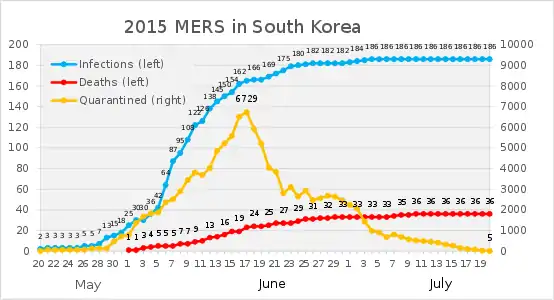

South Korea

In May 2015, the first case in South Korea was confirmed in a man who had visited Saudi Arabia, United Arab Emirates and Bahrain.[79] Another man from South Korea, who was travelling to China, was diagnosed as the first case in China. So far, no Chinese citizen has been found infected.[80]

As of 27 June 2015, 19 people in South Korea have died from this outbreak, with 184 confirmed cases of infection.[81] There have been at least 6508 quarantined.[82][83][84][85][86][87]